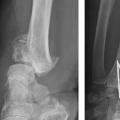

Au niveau métaphysaire le déplacement peut être postérieur ou antérieur (fig. 6). En ce qui concerne le déplacement postérieur, il est important de se souvenir que la surface articulaire regarde vers l’avant. En d’autres termes, dès que cela n’est plus le cas, même si la surface articulaire n’est pas orientée vers l’arrière, il s’agit d’un déplacement postérieur. Classiquement, le déplacement postérieur est lié à un mécanisme dit en compression-­extension, c’est-à-dire une chute sur la main, le poignet étant en extension (fig. 7). Le déplacement est dit antérieur s’il y a une exagération de l’orientation antérieure de l’épiphyse radiale. Ce déplacement est classiquement lié à un mécanisme dit en compression-flexion, c’est-à-dire une chute sur la main, le poignet étant en flexion (fig. 7). La plupart du temps, ce déplacement postérieur ou antérieur s’accompagne également d’un déplacement externe, avec un tassement au niveau de la corticale latérale (fig. 8). Outre le déplacement antérieur, postérieur ou latéral, il est très important d’analyser au niveau du foyer de fracture métaphysaire l’importance de la comminution qui peut être uniquement postérieure, ou antérieure, ou circonférentielle, ce qui conditionne la stabilité de la fracture et oriente vers le type d’ostéosynthèse à réaliser.

L’analyse de l’épiphyse va permettre de déterminer si la fracture est articulaire ou extra-articulaire. Dans la très grande majorité des cas, la fracture est articulaire. Il existe très fréquemment un fragment postéromédial qu’il est important de rechercher car il faudra le stabiliser lors du traitement. Mais la fracture articulaire peut être plus complexe, en T ou en croix (fig. 9). Enfin, il peut exister des enfoncements de fragments ostéochondraux à l’intérieur du spongieux épiphysaire (appelé par les Anglo-Saxons « die punch »). Sur les fragments épiphysaires s’attachent les ligaments radiocarpiens. Ainsi, une traction dans l’axe permet, par le biais de ses ligaments (effet de ligamentotaxis), de réduire au moins partiellement la fracture. En revanche, les fragments ostéochondraux qui sont enfoncés dans le spongieux n’ont pas d’attaches ligamentaires et ne se réduisent pas par les manœuvres de traction. Il peut arriver que les fractures soient uniquement épiphysaires. C’est le cas des fractures dites marginale antérieure, marginale postérieure et cunéenne externe. Cette dernière est importante à connaître et à dépister car elle s’accompagne relativement fréquemment de lésion ligamentaire intracarpienne, notamment scapholunaire.